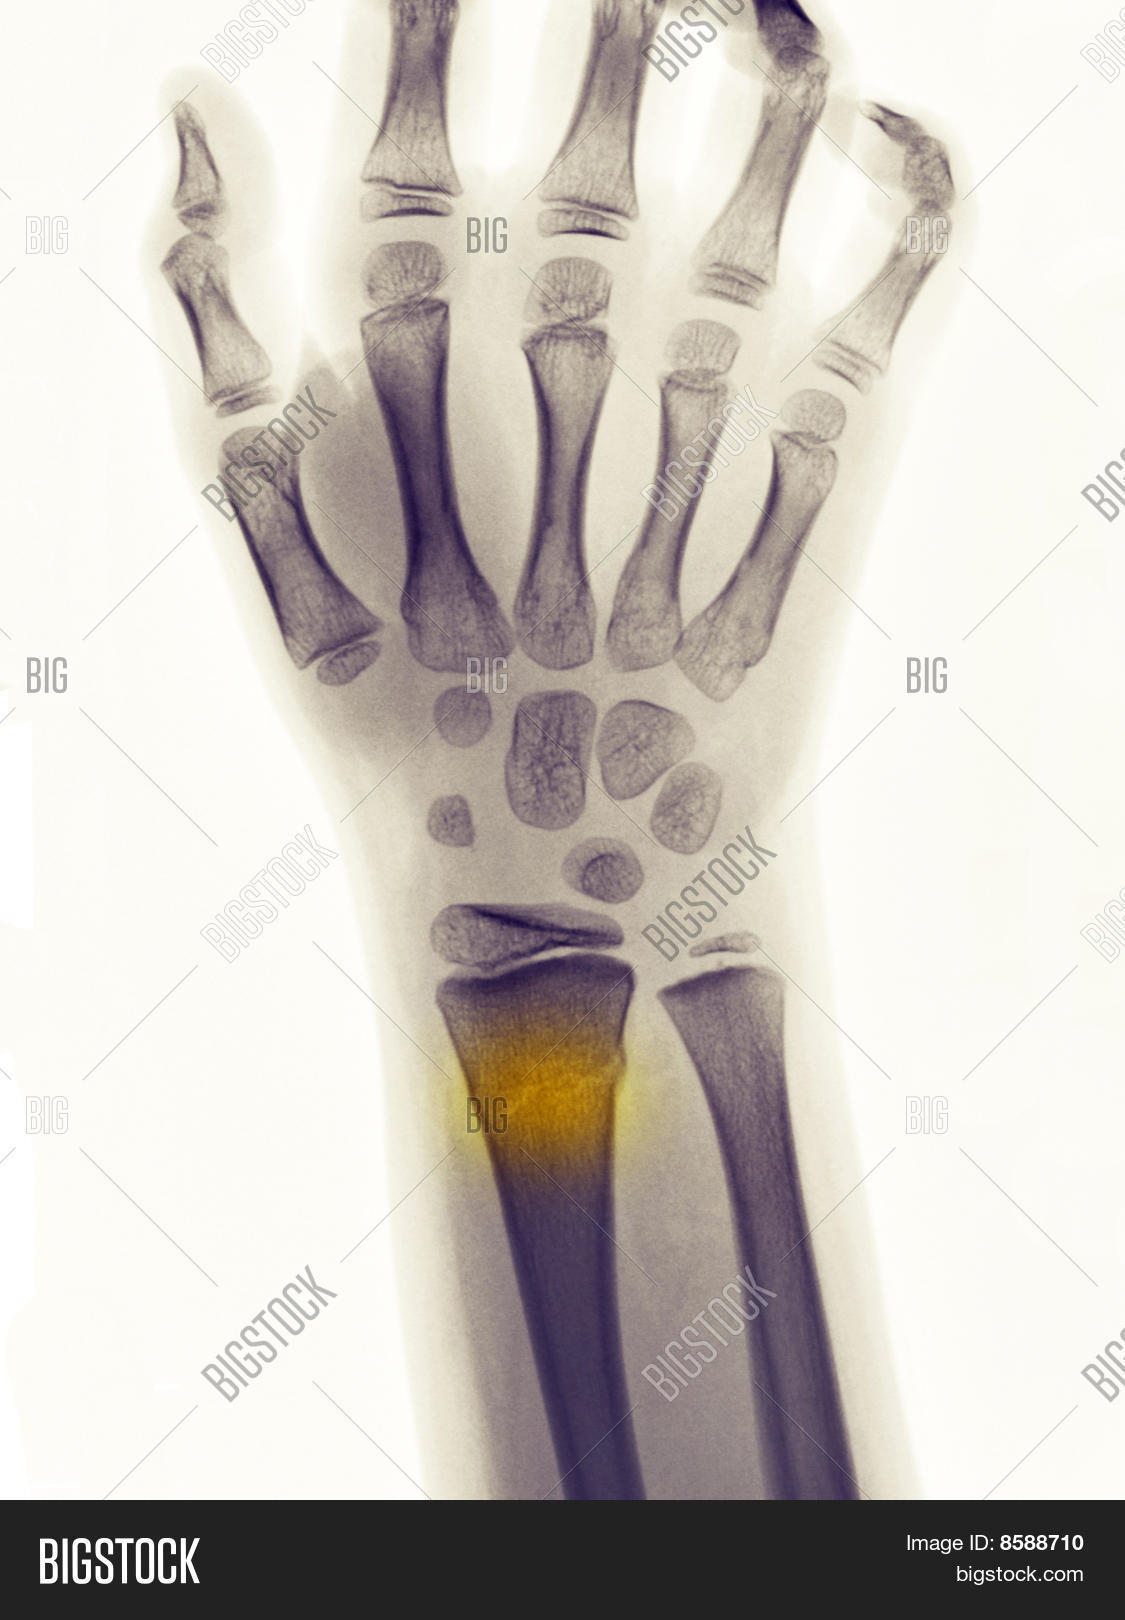

From www.bigstockphoto.com

Xray Showing Greenstick Fracture Image & Photo Bigstock Greenstick Fracture X-Ray Paediatric forearm fractures can be practically classified considering 3 main characteristics: The rest of the bones on both sides are intact. Greenstick fractures usually affect the forearm and upper arm bones, and are often caused by falling on an outstretched arm. Due to skeletal immaturity, they may present as greenstick fractures. A greenstick injury comprises a. Children have more pliable. Greenstick Fracture X-Ray.

From www.dreamstime.com

Xray of the Wrist. Greenstick Fracture of the Radius Stock Photo Greenstick Fracture X-Ray Due to skeletal immaturity, they may present as greenstick fractures. They may also use magnetic. Paediatric forearm fractures can be practically classified considering 3 main characteristics: A greenstick injury comprises a. The rest of the bones on both sides are intact. Greenstick fractures usually affect the forearm and upper arm bones, and are often caused by falling on an outstretched. Greenstick Fracture X-Ray.